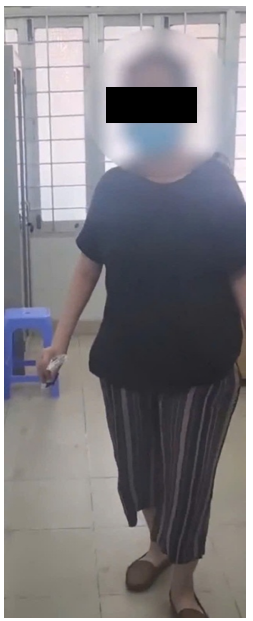

A 55-year-old female with no significant medical history and no previous internal or autoimmune diseases was examined at the Musculoskeleton Clinic due to progressive leg weakness over the last 3 years. In March 2022, she started experiencing fatigue and mild weakness along with numbness in both legs, without any lower back pain, and was still able to work and perform her usual activities. She visited the clinic and was diagnosed with uterine fibroids that were compressing the nerve and muscle, leading to her undergoing a hysterectomy. Nevertheless, she continued to have leg weakness after the surgery. When the patient arrived at the musculoskeletal clinic, she had to place both hands on the floor in order to stand up because of weakness in both lower limbs (Figure 1). The progression of the patient's illness is as follows in Table 1.

Figure 1: The patient had weak muscles in the limbs, difficulty standing up, and need to place both hands on the ground to stand.

Figure 2: After using Rituximab for two months, the patient was able to walk.

However, there has been increasing interest in the role of B lymphocytes, given the success of Rituximab, a monoclonal antibody targeting CD20 on B cells, in treating refractory autoimmune diseases [4]. Rituximab initiates B cell lysis through complement activation and antibody-dependent cell-mediated cytotoxicity. Furthermore, several features of Anti-SRP myopathy suggest a role for humoral immunity in its pathogenesis, including deposition of membrane attack complexes on sarcolemma and small blood vessels in muscle fascicles, non-inflammatory small vessel damage, and the correlation between autoantibody levels and disease activity. These findings imply that humoral immune responses, with B cells as the primary cellular component, play a significant role in the disease's pathogenesis. Indeed, in a case series by Ritu Valiyil et al, eight patients with Anti-SRP myopathy who did not respond to initial treatment with corticosteroids and conventional immunosuppressive agents showed significant improvement in muscle strength and enzyme levels following rituximab infusion [10]. In our case, after discussion with the patient and obtaining consent, rituximab was administered in combination with corticosteroid pulse therapy, given over two cycles, 2 weeks apart. The follow-up visit revealed significant clinical improvement (in muscle strength and HAQ-DI score) and a decrease in muscle enzyme levels (Figure 2).